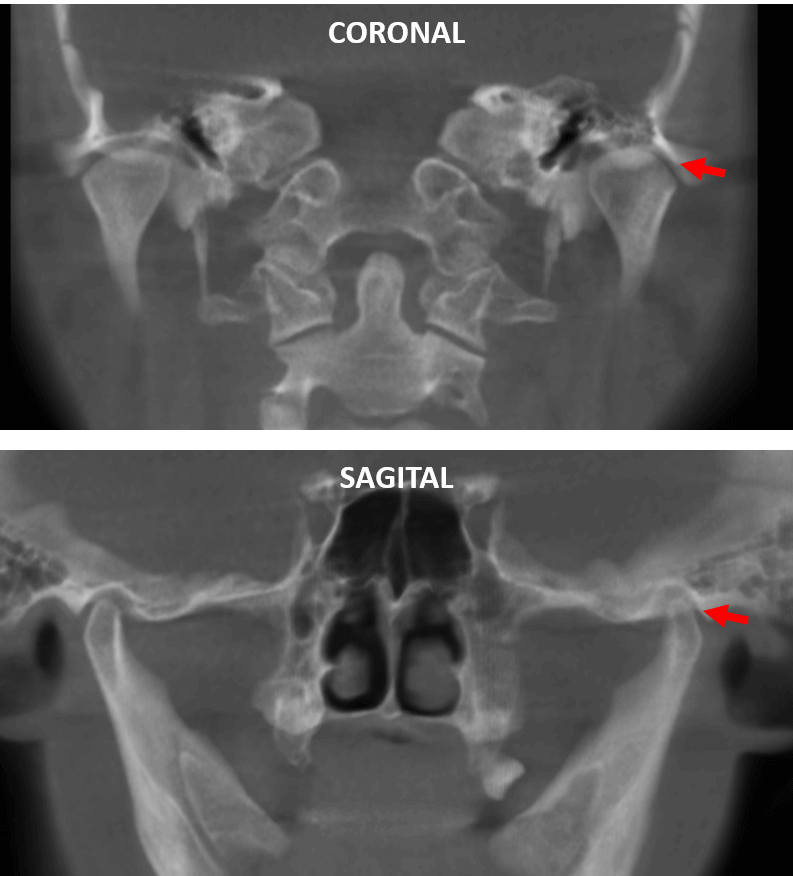

Fig.2

En las imágenes comparativas de ambos lados de la ATM (Fig.2) se observa la disminución del espacio articular en el corte coronal (superior) en el lado izquierdo y a nivel del polo lateral (flecha roja). Así mismo, se observa en el corte sagital (inferior) en el mismo un aparente cambio la morfología del cóndilo mandibular.